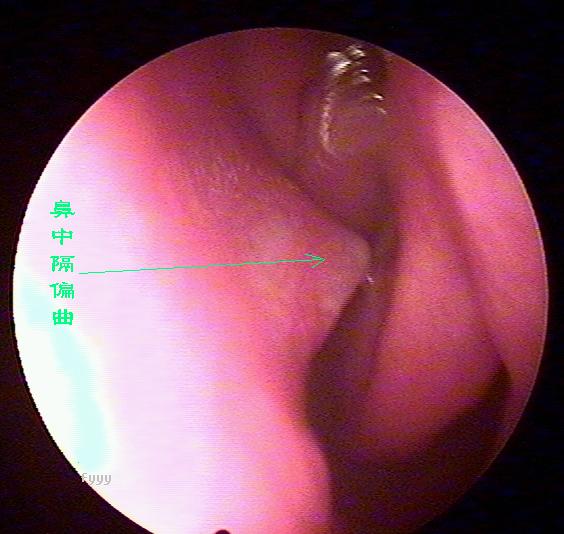

鼻内窥镜下的鼻中隔偏曲

老流鼻血可能是鼻中隔偏曲惹的祸,鼻中隔偏曲部位经常会出现血管畸形,而且这里的粘膜也相对较薄,受气流、尘埃等刺激后容易破损、出血,主要症状为:交替性或持续性鼻塞,头痛,鼻出血及流脓涕等。且难以痊愈,经常发作。西安新城中大耳鼻喉医院耳鼻喉科推出的,快速无痛治疗鼻中隔偏曲。

2、鼻出血:鼻出血是鼻中隔偏曲较为常见的症状之一。发生在偏曲之凸面、骨棘或骨嵴的先进部,此处粘膜薄。常受气流和尘埃刺激易发生糜烂而出血。老是在洗脸的时候流鼻血是什么原因 ?